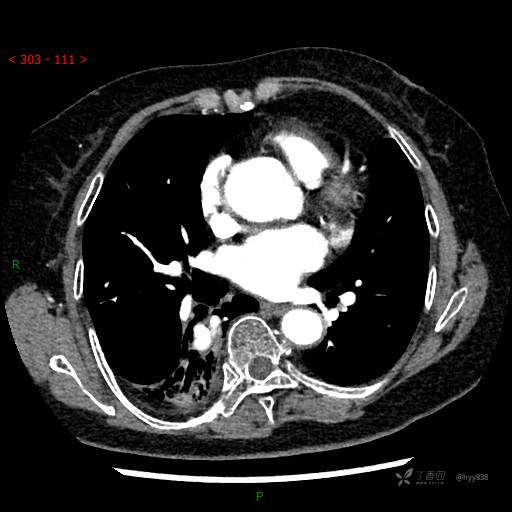

增强动脉期